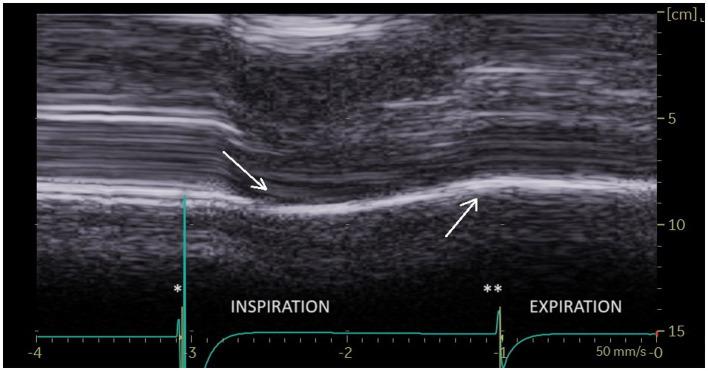

On paralyzed hemidiaphragm, thickening was less than 20% in all patients during deep inspiration. Thinning was recorded in 53% of cases. In some cases, the recording of the thickening could be difficult. The study of motion during voluntary sniffing reported a paradoxical excursion in all but one patient. During quiet breathing, an absence of movement or a paradoxical displacement was observed. During deep inspiration, a paradoxical motion at the beginning of inspiration followed by a reestablishment of movement in the cranio-caudal direction was seen in 82% of cases. In some patients, there was a lack of movement followed, after an average delay of 0.4 s, by a cranio-caudal excursion. Finally, in 4 patients no displacement was recorded. Evidence of hyperactivity (increased inspiratory thickening and excursion) of contralateral non-paralyzed hemidiaphragm was observed.